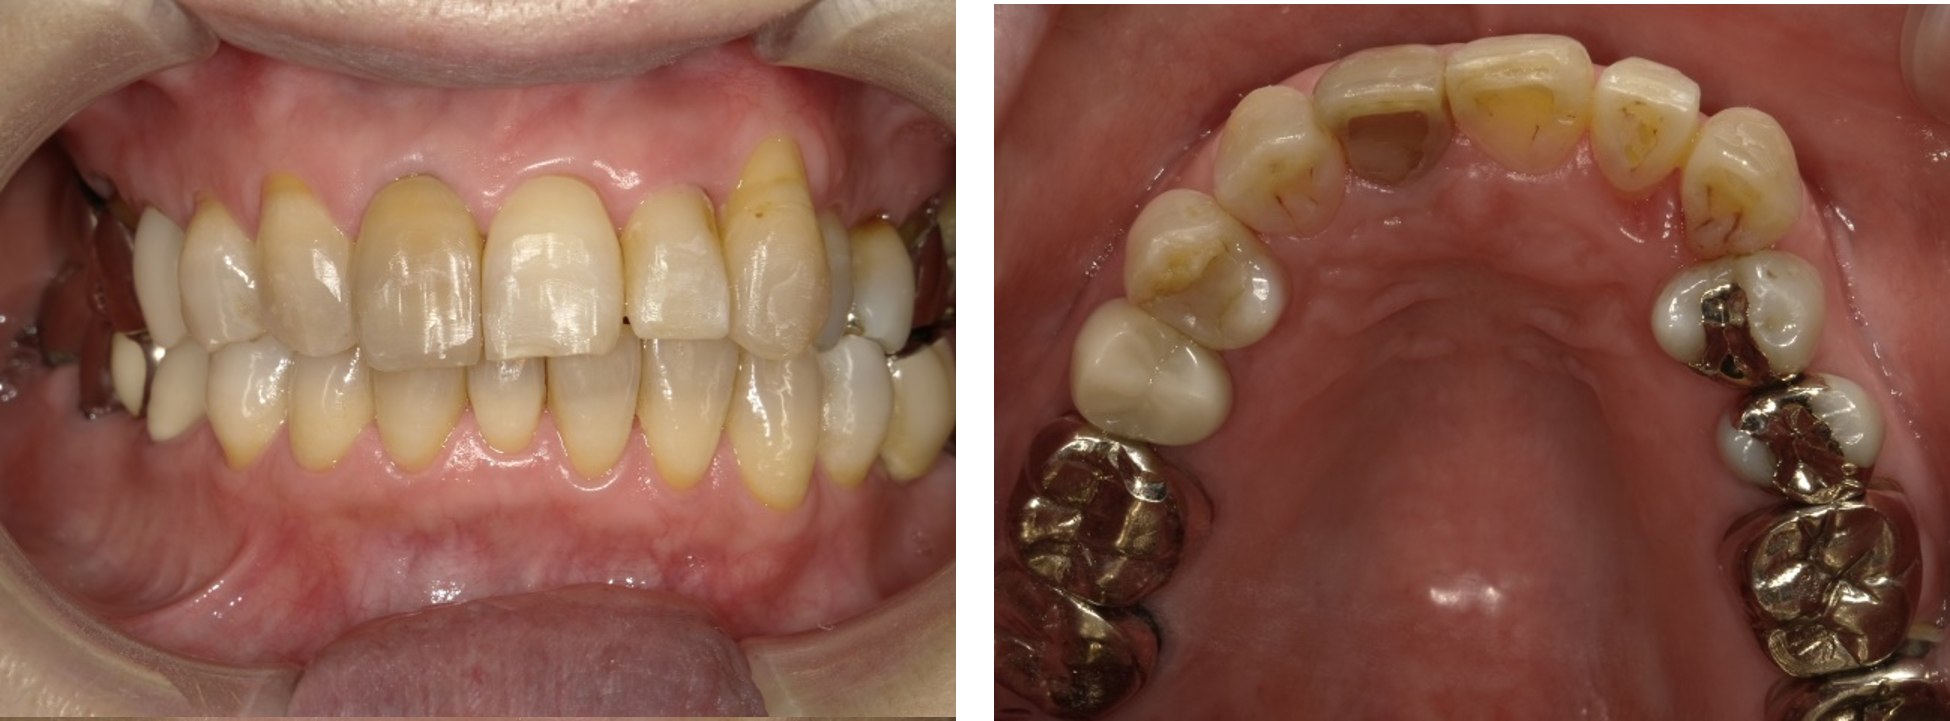

実際に当院で部分矯正治療を受けられた方の感想です。

「はじめは装置に慣れずに口内炎ができたり、歯磨きでも苦労しましたが、だんだん動いてくる自分の歯を見ると、勇気が湧いてきました。治療が終わるころには、通い始めたころとは見違えるように、綺麗になっていて長年のコンプレックスから解放されました。

矯正治療はとても高いと聞いていたけど、部分矯正なら20~30万で済むし、何より健康な歯を大きく削られないのが魅力です」